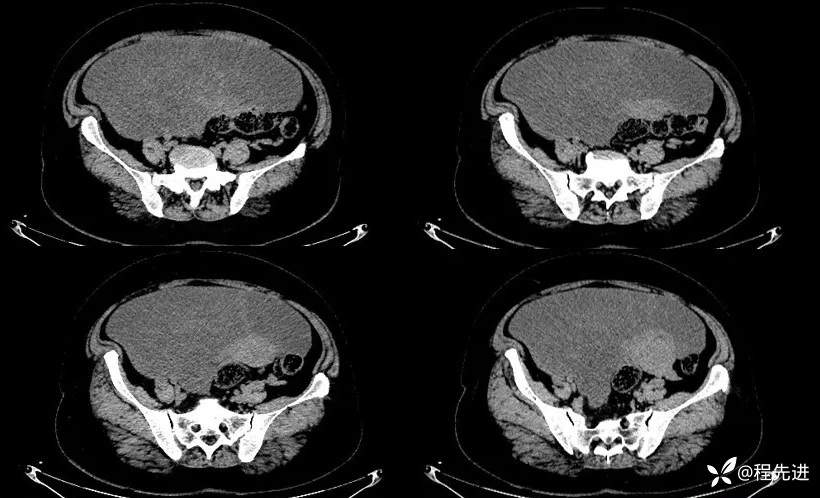

平扫: